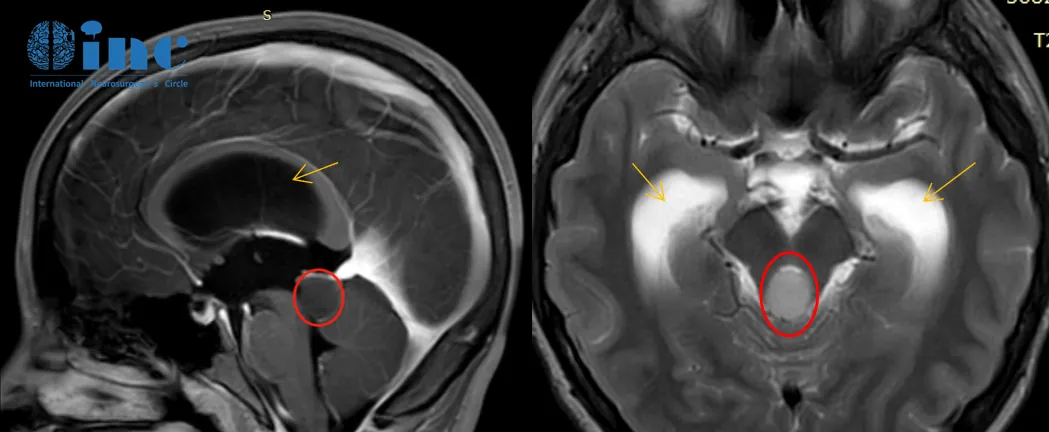

2018年2月头颅核磁检查:脑干-中脑顶盖占位伴梗阻性脑积水

2020年8月头颅核磁检查:肿瘤较前增大,脑积水较前明显加重

2020年的影像检查发现脑干-中脑顶盖占位伴幕上脑室扩张积水,较2018年的影像检查显示肿瘤有明显强化生长迹象。

手术经正中幕下小脑上入路手术,术中使用神经电生理监测和MRI辅助,保证神经功能、重要脑组织和大脑静脉不受损伤。由于肿瘤基底部和脑干关系密切、紧邻小脑,教授在保全患者正常功能神经和脑干等重要脑组织的前提下,完成肿瘤近全切手术,病理结果为脑干-中脑顶盖毛细胞型星形细胞瘤,这是一种预后较好的胶质瘤,通常手术全切或近全切除可获得良好预后。

术后3个月回访时,小永复查MRI表明肿瘤已经很好地切除了。由于术前伴有长期的梗阻性脑积水,导致脑室扩大,脑积水吸收不良仍然存在,还需要一段时间的康复治疗。但患者的整体状态已经恢复得很好了,可以逐步回归正常的生活。术后1年半,小永不仅已经回归正常生活和学习,还以优异成绩考入名校。